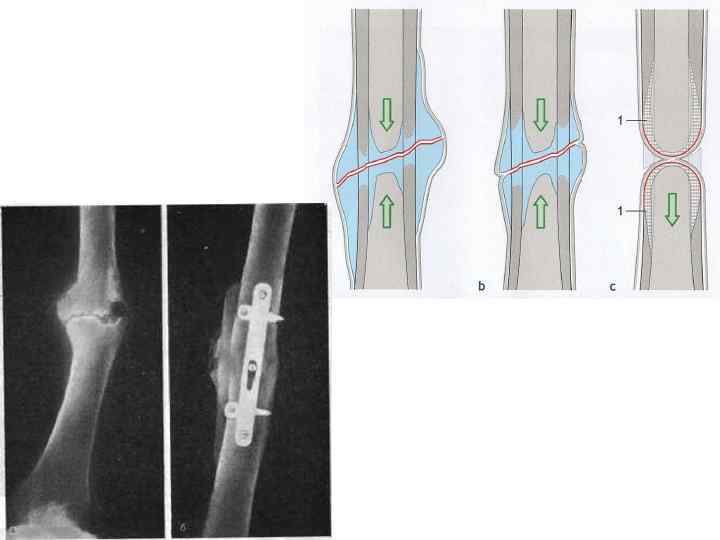

ВОПРОС № 27. Ложный сустав и его причины Ложный сустав — вариант процесса сращения костных отломков, когда по прошествии двойного среднего срока, необходимого для формирования полноценной костной мозоли, рентгенологические признаки консолидации отсутствуют

Псевдоартроз (др. название «неоартро з» ) — это ложный сустав, образовавшийся на несвойственном ему месте вследствие длительно существующего вывиха или внутрисуставного перелома. Врожденный вывих бедра может стать причиной возникновения псевдоартроза.

ОСНОВНЫЕ ПРИЧИНЫ • Заболевания, при которых нарушается обмен веществ и репаративная регенерация костной ткани • Дефекты оперативного вмешательства (непрочная фиксация) • Ошибки послеоперационного лечения (раннее устранение фиксации) • Ошибки консервативного лечения (смещение отломков под гипсом) • Нагноение (остеомиелит)

ЛЕЧЕНИЕ Накостный остеосинтез при гипертрофическом ложном суставе